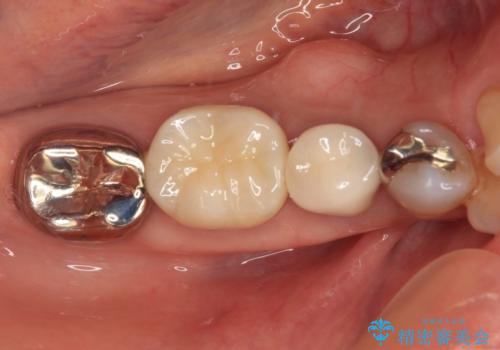

銀歯を外したところ、非常に大きなむし歯が認められましたが、神経組織には及んでおらず、速やかにオールセラミッククラウンによる補綴治療を行いました。